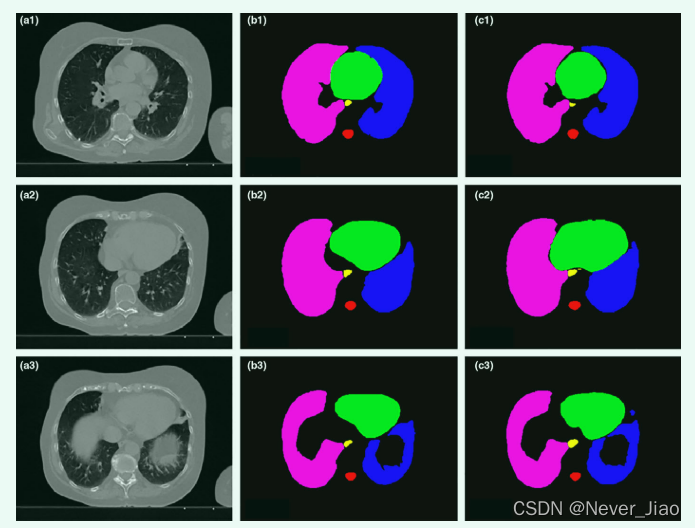

图 3 和图 4 显示了使用所提出的 U-Net-GAN 方法对一名患者进行的 2D 和 3D 分割结果。所提出的方法分割双侧肺、心脏和脊髓,并成功描绘了食道。使用我们的方法获得的 OAR 与ground truth轮廓非常相似。

Fig.3 (a) 一名患者的三个横向计算机断层扫描切片,以及从(b)手动轮廓(ground truth)和(c)所提出的方法中获得的相应风险器官轮廓。

Fig.4 通过(a)手动轮廓和(b)所提出的方法获得的图 3 中同一患者的风险器官轮廓的 3D 可视化。